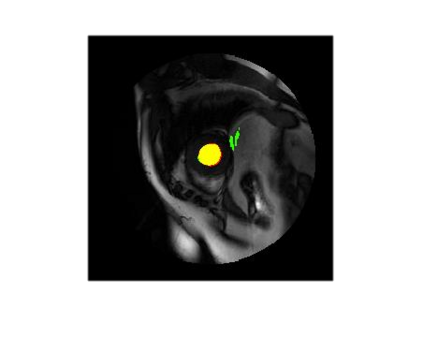

Deep Convolutional Neural Networks (DCNNs) are used extensively in biomedical image segmentation. However, current DCNNs usually use down sampling layers for increasing the receptive field and gaining abstract semantic information. These down sampling layers decrease the spatial dimension of feature maps, which can be detrimental to semantic image segmentation. Atrous convolution is an alternative for the down sampling layer. It increases the receptive field whilst maintains the spatial dimension of feature maps. In this paper, a method for effective atrous rate setting is proposed to achieve the largest and fully-covered receptive field with a minimum number of atrous convolutional layers. Furthermore, different atrous blocks, shortcut connections and normalization methods are explored to select the optimal network structure setting. These lead to a new and full-scale DCNN - Atrous Convolutional Neural Network (ACNN), which incorporates cascaded atrous II-blocks, residual learning and Fine Group Normalization (FGN). Application results of the proposed ACNN to Magnetic Resonance Imaging (MRI) and Computed Tomography (CT) image segmentation demonstrate that the proposed ACNN can achieve comparable segmentation Dice Similarity Coefficients (DSCs) to U-Net, optimized U-Net and hybrid network, but with significantly reduced trainable parameters due to the use of full-scale feature maps and therefore computationally is much more efficient for both the training and inference.